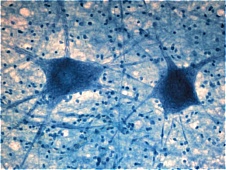

ΠΡΠΊΡΡcΡΠ²Π΅Π½Π½ΡΠΌ ΠΏΡΡΠ΅ΠΌ ΠΏΠΎΠ»ΡΡΠΈΠ»ΠΎΡΡ ΡΠΎΠ·Π΄Π°ΡΡ Π½Π°ΡΡΠΎΡΡΠΈΠ΅ Π½Π΅ΠΉΡΠΎΠ½Ρ Π³ΠΎΠ»ΠΎΠ²Π½ΠΎΠ³ΠΎ ΠΌΠΎΠ·Π³Π° ΠΈΠ· ΠΎΠ±ΡΠΊΠ½ΠΎΠ²Π΅Π½Π½ΡΡ ΠΊΠ»Π΅ΡΠΎΠΊ ΡΠΏΠΈΠ΄Π΅ΡΠΌΠΈΡΠ°, ΡΠΎ Π΅ΡΡΡ ΡΠ΅Π»ΠΎΠ²Π΅ΡΠ΅ΡΠΊΠΎΠΉ ΠΊΠΎΠΆΠΈ. Π‘Π°ΠΌΡΠΌ Π½Π΅Π²Π΅ΡΠΎΡΡΠ½ΡΠΌ ΡΠ²Π»ΡΠ΅ΡΡΡ ΡΠΎΡ ΡΠ°ΠΊΡ, ΡΡΠΎ Π² ΠΈΡΡΠ»Π΅Π΄ΠΎΠ²Π°Π½ΠΈΠΈ Π½ΠΈΠΊΠ°ΠΊΠΈΠΌ Π±ΠΎΠΊΠΎΠΌ Π½Π΅ Π±ΡΠ»ΠΈ Π·Π°Π΄Π΅ΠΉΡΡΠ²ΠΎΠ²Π°Π½Ρ ΡΡΠ²ΠΎΠ»ΠΎΠ²ΡΠ΅ ΠΊΠ»Π΅ΡΠΊΠΈ, ΠΈΠ· ΠΊΠΎΡΠΎΡΡΡ ΠΎΠ±ΡΡΠ½ΠΎ ΠΈ ΠΏΡΠΎΠ΄ΡΡΠΈΡΡΡΡ ΠΊΠ»Π΅ΡΠΊΠΈ Π΄ΡΡΠ³ΠΈΡ ΠΎΡΠ³Π°Π½ΠΎΠ².

ΠΡΠ»ΠΈ Π΄Π°Π»ΡΠ½Π΅ΠΉΡΠΈΠ΅ ΠΈΡΡΠ»Π΅Π΄ΠΎΠ²Π°Π½ΠΈΡ ΠΎΠΊΠ°ΠΆΡΡΡΡ ΡΡΠΏΠ΅ΡΠ½ΡΠΌΠΈ, Π½Π°Ρ ΠΆΠ΄Π΅Ρ ΡΠΎ Π·ΠΎΠ»ΠΎΡΠΎΠ΅ Π²ΡΠ΅ΠΌΡ, ΠΊΠΎΠ³Π΄Π° ΠΎΠ±ΡΠΊΠ½ΠΎΠ²Π΅Π½Π½Π°Ρ ΡΠ΅Π»ΠΎΠ²Π΅ΡΠ΅ΡΠΊΠ°Ρ ΠΊΠΎΠΆΠ° ΡΡΠ°Π½Π΅Ρ Π²Π΅ΡΠ½ΡΠΌ ΠΏΠΎΠΌΠΎΡΠ½ΠΈΠΊΠΎΠΌ Π² Π»Π΅ΡΠ΅Π½ΠΈΠΈ Π½Π΅Π²Π΅ΡΠΎΡΡΠ½ΠΎΠ³ΠΎ ΠΊΠΎΠ»ΠΈΡΠ΅ΡΡΠ²Π° ΡΠ΅Π»ΠΎΠ²Π΅ΡΠ΅ΡΠΊΠΈΡ Π±ΠΎΠ»Π΅Π·Π½Π΅ΠΉ, Π² ΡΠ°ΡΡΠ½ΠΎΡΡΠΈ, ΠΌΠ½ΠΎΠΆΠ΅ΡΡΠ²Π° ΡΠ΅ΡΡΠ΅Π·Π½ΡΡ Π·Π°Π±ΠΎΠ»Π΅Π²Π°Π½ΠΈΠΉ Π½Π΅ΡΠ²Π½ΠΎΠΉ ΡΠΈΡΡΠ΅ΠΌΡ, ΠΎΡ ΠΊΠΎΡΠΎΡΡΡ Π΄ΠΎΡΠ΅Π»Π΅ Π½Π΅Ρ ΡΠ½ΠΈΠ²Π΅ΡΡΠ°Π»ΡΠ½ΠΎΠ³ΠΎ ΠΈ ΡΡΡΠ΅ΠΊΡΠΈΠ²Π½ΠΎΠ³ΠΎ Π»Π΅ΠΊΠ°ΡΡΡΠ²Π°.